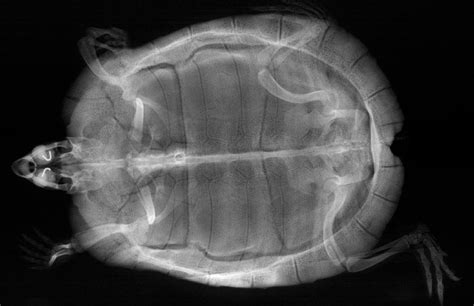

Hey there, fellow turtle enthusiasts ! If you’re a proud parent to one of these amazing shelled creatures, you already know they’re pretty unique pets. But here’s something super important that many new owners might not realize: turtle X-rays are an absolutely critical diagnostic tool for ensuring their long-term health and well-being. Unlike a dog or cat where you can easily spot a limp or a cough, turtles are masters of disguise, often hiding illness until it’s quite advanced. Their very anatomy, that impressive shell, which is part of their skeletal system, makes internal examination incredibly challenging without specialized tools. This is where the magic of veterinary imaging, specifically X-rays, comes into play, offering a non-invasive, yet incredibly detailed, look into their internal world. We’re talking about getting a full picture of their bones, organs, and any potential issues brewing beneath that protective exterior.

Think about it, guys: a turtle’s shell is designed to protect them, making it really difficult for vets to perform a thorough physical examination of their internal organs. You can’t just feel their abdomen for lumps or check their lungs for fluid in the same way you would with a furry friend. This is precisely why turtle X-rays become an indispensable part of their veterinary care . These images allow experienced reptile vets to literally see through the shell and bones, identifying a whole host of problems that would otherwise go undetected until symptoms become severe, and often, much harder to treat. From common ailments like metabolic bone disease (MBD) , which can cause significant skeletal deformities and pain, to more urgent concerns like pneumonia or the presence of foreign bodies in their digestive tract, an X-ray can provide immediate, actionable insights. For female turtles, X-rays are also the go-to method for diagnosing serious conditions like egg binding (dystocia) , a life-threatening situation where eggs get stuck internally. Early detection is truly the name of the game when it comes to reptile health, and X-rays empower veterinarians to catch problems before they spiral out of control. It’s not just about treating illness, but also about offering incredible value in preventative care , allowing vets to monitor bone density, organ size, and overall internal structure over time. Investing in these diagnostic images means investing in a longer, happier, and healthier life for your cherished shelled companion. So, the next time your vet suggests an X-ray for your turtle, understand that they’re recommending one of the most powerful tools available to truly understand what’s happening inside.

Alright, so we’ve established why turtle X-rays are super important, but let’s get down to the nitty-gritty: what exactly can these incredible images show us ? When your turtle undergoes an X-ray, it’s like getting a secret blueprint of their internal architecture, revealing a wealth of information crucial for accurate diagnosis. It’s honestly amazing what a skilled reptile veterinarian can deduce from a few well-positioned radiographs. Let’s break down some of the most common and critical conditions that these powerful turtle X-ray diagnostics can unveil, giving vets the information they need to formulate the best possible treatment plan for your little (or not-so-little) shelled buddy.

One of the most frequent findings on a turtle X-ray is related to bone health , particularly conditions like Metabolic Bone Disease (MBD) . This is a very common issue in captive reptiles, often due to improper diet (lack of calcium or vitamin D3) and inadequate UV light exposure. On an X-ray, MBD can manifest as generalized poor bone density, meaning the bones appear thinner and less opaque than they should. Vets might also observe shell deformities , such as pyramiding or softening, or even fractures that have occurred due to weakened bones. Identifying MBD early through X-rays allows for dietary adjustments and environmental modifications before the condition becomes debilitating. Another critical finding is evidence of respiratory issues , such as pneumonia . Turtles with pneumonia often present with lethargy and nasal discharge, but an X-ray can confirm the presence of fluid or inflammation in the lungs. You might see a hazy or cloudy appearance in the lung fields, or even a consolidation indicating severe infection. This is a very serious condition for turtles, and X-ray confirmation is vital for immediate treatment with appropriate antibiotics.

Then there’s the incredibly common and often life-threatening problem of foreign body ingestion . Turtles, being curious creatures, sometimes eat things they shouldn’t – gravel, plastic pieces, or even small toys. An X-ray is the gold standard for identifying these objects within the digestive tract. Depending on the material, they will appear as opaque structures against the softer tissue. Locating a foreign body is the first step towards deciding on the best course of action, whether it’s monitoring for natural passage, or more often, surgical removal. For female turtles, one of the most urgent conditions identified by turtle X-rays is egg binding (dystocia) . This is when a female turtle is unable to lay her eggs. X-rays clearly show the presence of eggs and their location within the reproductive tract. Vets can assess the number, size, and position of the eggs, which helps them determine if medical intervention (like oxytocin injections) or surgical removal is necessary. Without an X-ray, diagnosing egg binding would be incredibly difficult, often leading to fatal complications.

Furthermore, turtle X-ray imaging can reveal the presence of bladder stones, also known as uroliths . These calcified stones can form in the bladder and cause significant pain and obstruction. On an X-ray, they appear as distinct, dense white structures. Identifying them allows vets to plan for surgical removal, relieving the turtle’s discomfort. Fractures or trauma to the shell or bones, perhaps from a fall or an unfortunate accident, are also clearly visible. X-rays help assess the extent of the damage and guide the repair process. Even tumors or internal masses can sometimes be detected, appearing as abnormal densities or structures within the body cavity. While an X-ray might not provide a definitive diagnosis of cancer, it can indicate the presence of an abnormality that warrants further investigation, like a biopsy or more advanced imaging. It’s truly a testament to the power of this diagnostic tool that so many varied and vital pieces of information can be gathered from a simple, non-invasive image. Understanding these potential revelations allows pet parents to appreciate the depth of information their vet is working with to care for their cherished reptile. So, yeah, when your vet points to those grey and white images, they’re literally decoding your turtle’s internal story!